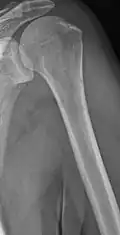

The diagnostic examination of a person with suspected multiple myeloma typically includes a skeletal survey. This is a series of X-rays of the skull, axial skeleton, and proximal long bones. Myeloma activity sometimes appears as "lytic lesions" (with local disappearance of normal bone due to resorption) or as "punched-out lesions" on the skull X-ray ("raindrop skull"). Lesions may also be sclerotic, which is seen as radiodense.[76] Overall, the radiodensity of myeloma is between −30 and 120 Hounsfield units (HU).[77] Magnetic resonance imaging is more sensitive than simple X-rays in the detection of lytic lesions. An MRI may supersede a skeletal survey, especially when vertebral disease is suspected. Occasionally, a CT scan is performed to measure the size of soft-tissue plasmacytomas. Nuclear Medicine Bone scans are typically not of any additional value in the workup of people with myeloma (no new bone formation; lytic lesions not well visualized on nuclear bone scan).

Multiple myeloma in the upper arm

Multiple myeloma in the upper arm -

Humerus with multiple myeloma lesions

Humerus with multiple myeloma lesions -

Same humerus before, with just subtle lesions

Same humerus before, with just subtle lesions